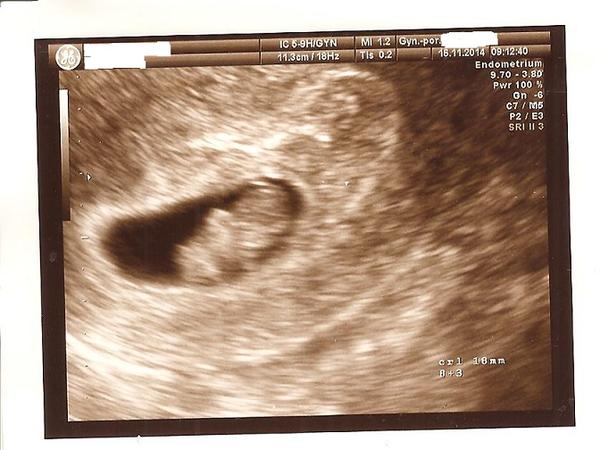

Holky, tak už to mám za sebou a musím říct, že už mi je líp. Včera jsem probrečela noc a byla jsem fakt na dně. Teď už jsem ráda, že půjdu zítra domů. Mohla za ´to obyčejná prohlídka u gynekologa a stěr z čípku a to jejich prohmatávání. Po tom jsem začala špinit, ale jelikož jsem se bála, tak jsem raději jela na pohotovost, kde mě zase prohmatávali, strkali do mě skla atd. No a potom se to rozjelo a začala jsem krvácet. Musím říct, že mi předtím dělali 2x ultrazvuk a miminka měli pravidelné ozvy a odpovídali jak plůdky tak i gestační váčky, týdnu vývoje. Prostě prosperující těhotenství. Ale po té poslední prohlídce, začalo to krvácení a trvalo dva dny. Celý týden jsem ležela v nemocnici a nechtěli mi udělat ultrazvuk, protože se báli, aby to ještě nezhoršili. Prostě si byli vědomi, že to tam moc rozšťourali. Miminka byla položena dole, takže o to to bylo více citlivé. No zkrátka za ten týden, co jsem ležela v nemocnici se tam vytvořil hematom z té krve a byl větší a větší a tím, že dělali ultrazvuk až po týdnu, tak na to přišli pozdě. Úplně je ten hematom zmáčknul a na UZ bylo vidět, jak jsou dutinky místo kulaté, tak velice zploštělé. Srdíčka se zastavili v neděli a UZ byl v úterý. Nikdy si neodpustím, že jsem k těm doktorům šla. Sestřička tady na gynekologii mi dnes říkala " holky v prvním trimestru, co nejmíň mačkání břicha a šťourání se v tom. Choďte jenom na UZ"....já na to nezapomenu do konce života. Promiňte, ale musela jsem se z toho vypsat. Už tu zase bulím.